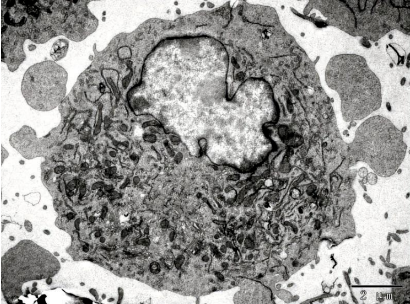

圖片來源:《腦腫瘤與神經組織電鏡圖譜》編著 孫異臨 人民衛生出版社